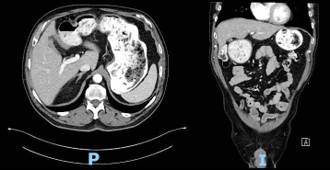

Computed Tomography (CT) scan performed at the time of admission revealed abundant food content with organized appearance in the abdomen (Figure 1), which was morphologically similar to that observed in previous CT scans. The findings supported chronic food retention with difficulty in gastric emptying at the level of pyloric antrum. Pharyngo-esophageal study revealed the presence of a bezoar occupying the entire gastric chamber with normal esophageal motility (Figure 2).